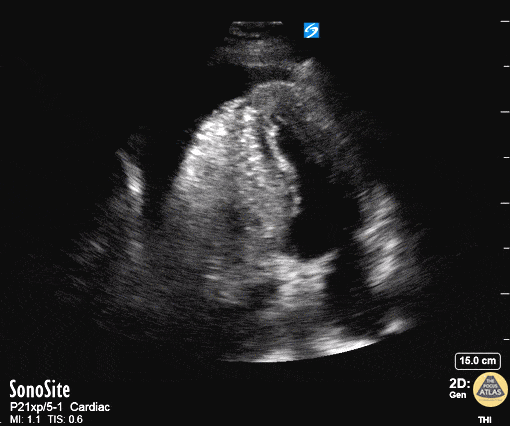

Pericardial Disease - Aortic Dissection with Tamponade - Apical

50 year old mandarin speaking man complains of vague central chest pain. You pursue a routine cardiac workup which is fairly normal. Upon discharging him, the nurse tells you his systolic in now in the 80's. Your RUSH exam and echo on this apical four demonstrate a pericardial tamponade with both: 1. Right ventricular DIASTOLIC collapse - dimpling of the right ventricular free wall during diastole while it should be filling 2. Right Atrial SYSTOLIC collapse - (but in atrial diastole) while the atrium should be filling Scroll to see the rest of the case for further images. Dr. Matthew Riscinti - Kings County Emergency Medicine, Dr. Benjamin Clearly - NYU Langone Emergency Medicine